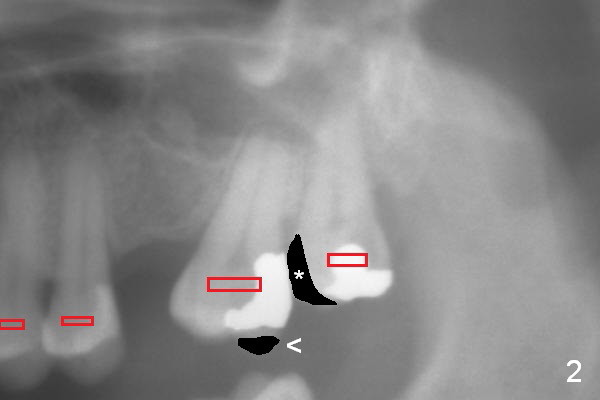

A 44-year-old lady requests restoring missing teeth at #14 (Fig.1 *) and 30. There is no buccopalatal width deficiency at #14, but the mesiodistal space needs to be expanded by distalizing the tooth #15 (arrow) after extraction of the tooth #16 (x). Placement of a longest mini-implant at the tuberosity area after socket healing is anticipated.

A second option for #14 is segmental orthodontic treatment. Initially keep the tooth #16 and mesial reduction (Fig.2 *). Place brackets between #11 and 16 (Fig.3 red) and open coil spring between #13 and 15.